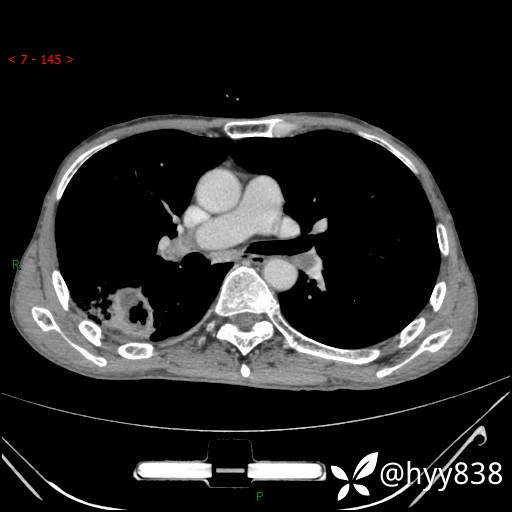

胸部CT平扫